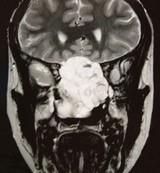

问题 女性,41岁,鼻腔流脓涕3年,鼻部面部肿胀1年,近来加重,MRI检查如图,请选择最可能诊断()

选项 A.鼻腔内囊肿 B.鼻腔内出血 C.鼻腔软骨瘤 D.鼻咽癌 E.鼻腔血管瘤

答案 C